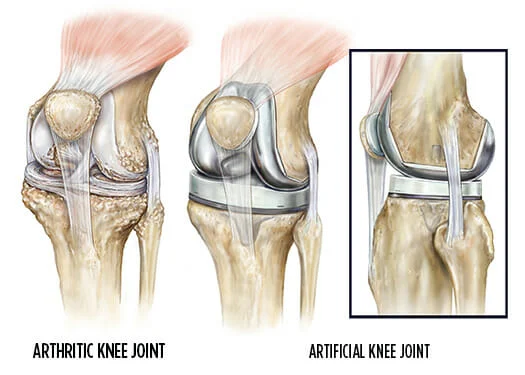

ماذا تتوقع من عملية استبدال الركبة؟

تُجرى عملية استبدال الركبة لمن يعانون من تلف شديد في مفصل الركبة مما يسبب لهم آلامًا مزمنة واختلالًا في وظائفها. وتُجرى عملية استبدال الركبة عندما لا تسفر جميع العلاجات الأخرى عن نتائج. وبشكل عام، يُعتبر المرضى الذين يعانون من هشاشة العظام ، في الفئة العمرية التي تتجاوز 50 عامًا، مرشحين رئيسيين لجراحة استبدال الركبة. الإجراء هذه عملية…